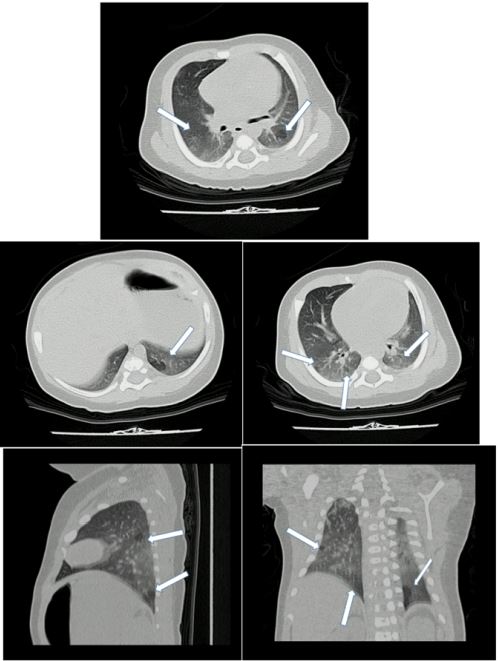

Durante la evolución del lactante, persistió la obstrucción de la vía aérea alta, dado por estridor, por lo que se le realizó una nasofibrolaringoscopia, en búsqueda de diagnósticos diferenciales; sin embargo, no se encontraron alteraciones y el ecocardiograma fue normal. Además, por persistencia de las sibilancias, de los signos de dificultad para respirar y los requerimientos de oxígeno, una tomografía de tórax evidenció un engrosamiento de las paredes bronquiales de predominio central, alteraciones en el parénquima pulmonar con signos de atrapamiento aéreo, afectación de la vía aérea pequeña y opacidades en vidrio esmerilado en los lóbulos inferiores (figura 3).

Luego de ello, se consideró que el paciente tenía una bronquiolitis constrictiva secundaria a infección previa por SARS-COV-2, por lo que se le inició manejo con esteroides sistémicos, beclometasona baja dosis y macrólido. Así, tuvo una adecuada evolución, aunque con persistencia de signos de dificultad respiratoria, dados por tirajes intercostales y taquipnea, aun cuando permitió disminuir los requerimientos de oxígeno por cánula nasal a 0,5 l/min.